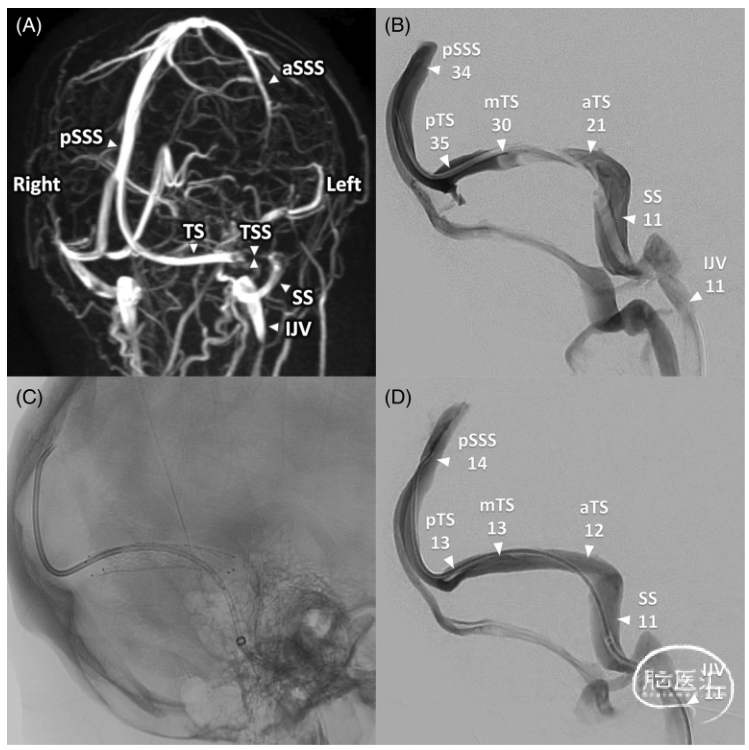

图1.(A)MRV的ATECO序列显示双侧横窦狭窄。aSSS,上矢状窦前段;IJV,颈内静脉;pSSS,上矢状窦后段;SS,乙状窦;TS,横窦;TSS,横窦狭窄。(B)支架植入前斜侧位静脉造影并测量压力(mmHg)。(C)沿左横窦狭窄段植入支架后的透视图像。(D)支架植入术后斜侧位静脉造影并测量压力。值得注意的是,在支架置入(B)之前,乙状窦(SS)和前横窦(aTS)之间有一个10mmHg的梯度,从21到11mmHg。支架植入术(D)后,从12到11mmHg的梯度仅为1mmHg。